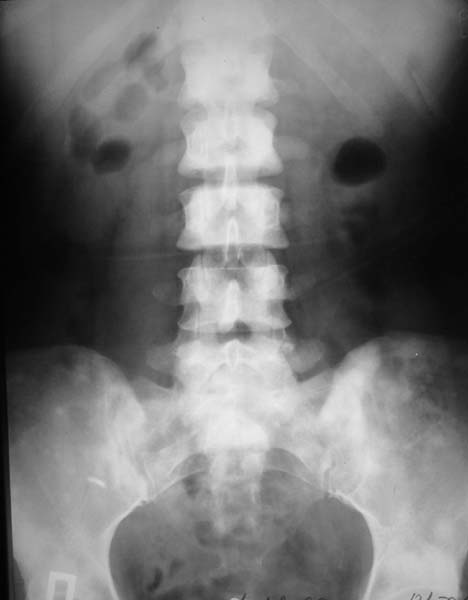

Женщина, 46 лет.

В течение четырех месяцев жалобы на боли в спине.

При МРТ (29.10.06) обнаружены диффузно-очаговые изменения в пояснично-крестцовом отделе позвоночника предположительно вторичного характера.

Остеосцинтиграфия 4.12.06. - активный остеобластический процесс в поясничном, нижнегрудном отделах позвоночника, костях таза. Местными онкологами онко-процесс исключен. Фтизиатрический и онкогематологический диагнозы исключены.